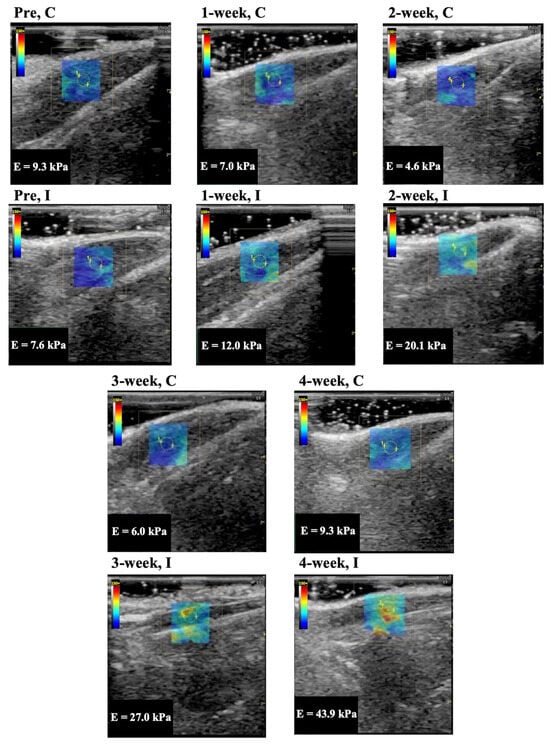

Representative longitudinal ultrasound shear wave elastography images of the rectus femoris, vastus lateralis, and vastus medialis muscle are shown in Figure 2, Figure 3, and Figure 4, respectively. In Group I, cyan, orange, and red colors increased during the immobilization period, suggesting an increased elastic modulus.

The elastic modulus of the rectus femoris, vastus lateralis, and vastus medialis muscle as determined by ultrasound shear wave elastography are shown in Figure 5A–C. The elastic modulus of the rectus femoris, vastus lateralis, and vastus medialis muscles in Group C were 8.6 ± 1.0, 7.4 ± 1.3, 7.6 ± 1.1 kPa (mean and standard deviation) in before experiment, 7.5 ± 1.4, 7.8 ± 0.8, 8.7 ± 0.5 kPa in 1 week, 7.4 ± 1.2, 7.1 ± 1.6, 8.0 ± 1.5 kPa in 2 weeks, 8.6 ± 1.2, 7.5 ± 0.9, 8.4 ± 0.7 kPa in 3 weeks, and 8.0 ± 1.0, 7.4 ± 1.0, 8.5 ± 0.7 kPa in 4 weeks, respectively. The elastic modulus of those muscles in Group I was 8.3 ± 1.2, 7.4 ± 1.1, 7.7 ± 1.1 kPa in the before experiment, 15.0 ± 1.4, 15.2 ± 2.2, 14.5 ± 1.5 kPa in 1 week, 20.1 ± 1.7, 19.6 ± 2.2, 18.9 ± 2.5 kPa in 2 weeks, 29.0 ± 2.1, 28.8 ± 1.7, 29.2 ± 2.4 kPa in 3 weeks, and 30.6 ± 2.7, 32.9 ± 4.0, 33.1 ± 3.4 kPa in 4 weeks, respectively. The elastic modulus for all periods in Group I was significantly higher (p = 0.0001 in all muscles) compared with the same periods in Group C. In Group I, the elastic modulus increased after more than 3 weeks of immobilization compared to the 1 and 2 week immobilizations.

Figure 2. Representative shear wave elastography of the rectus femoris muscle. C, control group; I, immobilization group; Pre, before the experiment; E, elastic modulus. The rectangle indicates the region of interest. The measurement circle was 5 mm in diameter.